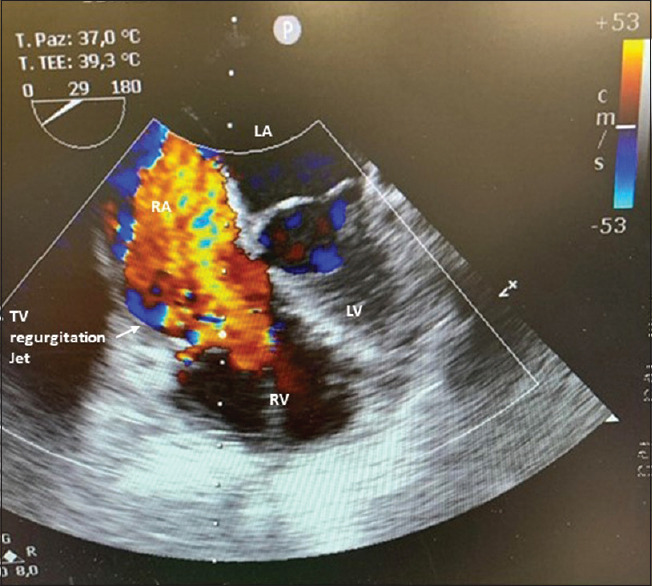

摘要:从右心室延伸出来的心脏肌瘤并不常见,这种罕见的情况可能与多种风险和不良预后有关。我们报告了一例右心室肌瘤患者的病例,该患者近期因动静脉畸形导致出血性中风。术前和术中的处理都极具挑战性,需要医疗团队做出若干艰难的选择,因此,必须采用多学科方法并进行效益风险评估,才能在紧急情况下及时决定手术切除,同时避免延误或不当治疗,在风险极高的情况下取得成功的结果。

Abstract: Cardiac myxomas extending from the right ventricle are uncommon and this rare condition is potentially associated with several risks and poor outcomes. We report the case of a patient with a right ventricular myxoma who had a recent haemorrhagic stroke due to an arteriovenous malformation. The preoperative and intraoperative managements were challenging and required several difficult choices by the medical team and consequently, a multidisciplinary approach and a benefit-risk evaluation were necessary to determinate timely surgical resection in an urgent situation, simultaneously avoiding delayed or improper treatments, achieving a successful outcome in a very high-risk situation.